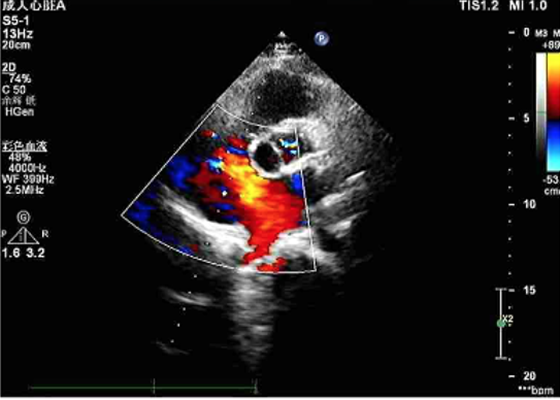

陈阿姨房间隔缺损封堵术前超声检查

家住常德澧县的陈阿姨是一位52岁的家庭主妇,半年来反复出现胸闷气促乏力,近一周多伴有明显咳嗽,慕名 来我院心胸外科就诊,心脏彩超提示为先天性心脏病:心脏超声检查提示陈阿姨的房间隔缺损范围较大、距上腔静脉的边缘较近。据了解,此种房间隔缺损在以前属于介入手术的“相对禁忌”。按照传统开胸手术,不仅风险大高,手术创伤大,而且术后恢复时间长,大多数患者都有恐惧心理。

在黄日茂教授、龙隆教授的带领下,以及麻醉科的支持配合下,经过约30分钟的努力,心胸外科团队在陈阿姨的心脏中植入了22mmASD封堵器,术中超声显示封堵器位置、形态良好,房间隔分流消失,听诊杂音消失,手术顺利结束,参加手术的医生护士和陈阿姨的家人一样露出了欣慰的笑容。